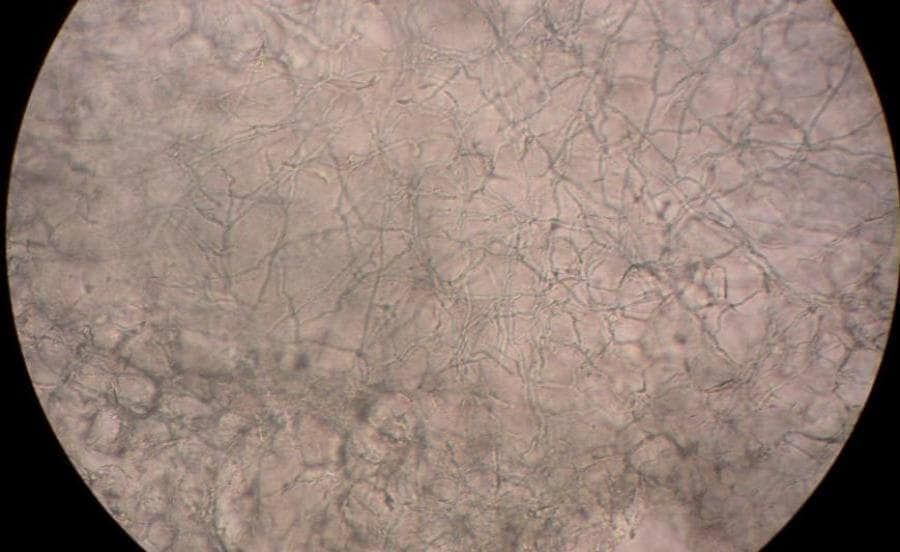

Eczeem laat zich kenmerken door verschillende verschijnselen die tegelijk of na elkaar kunnen voorkomen. De meest voorkomende symptomen zijn rode, gezwollen, schilferende plekken met een branderig en jeukend gevoel.

Bij droog eczeem kan de rode en schilferige huid gaan barsten met pijnlijke kloven als gevolg.

Bij nat eczeem zie je ook met vocht gevulde blaasjes of puistjes verschijnen. Als de blaasjes opengaan kan je last hebben van natte, plakkerige eczeem en wondjes.